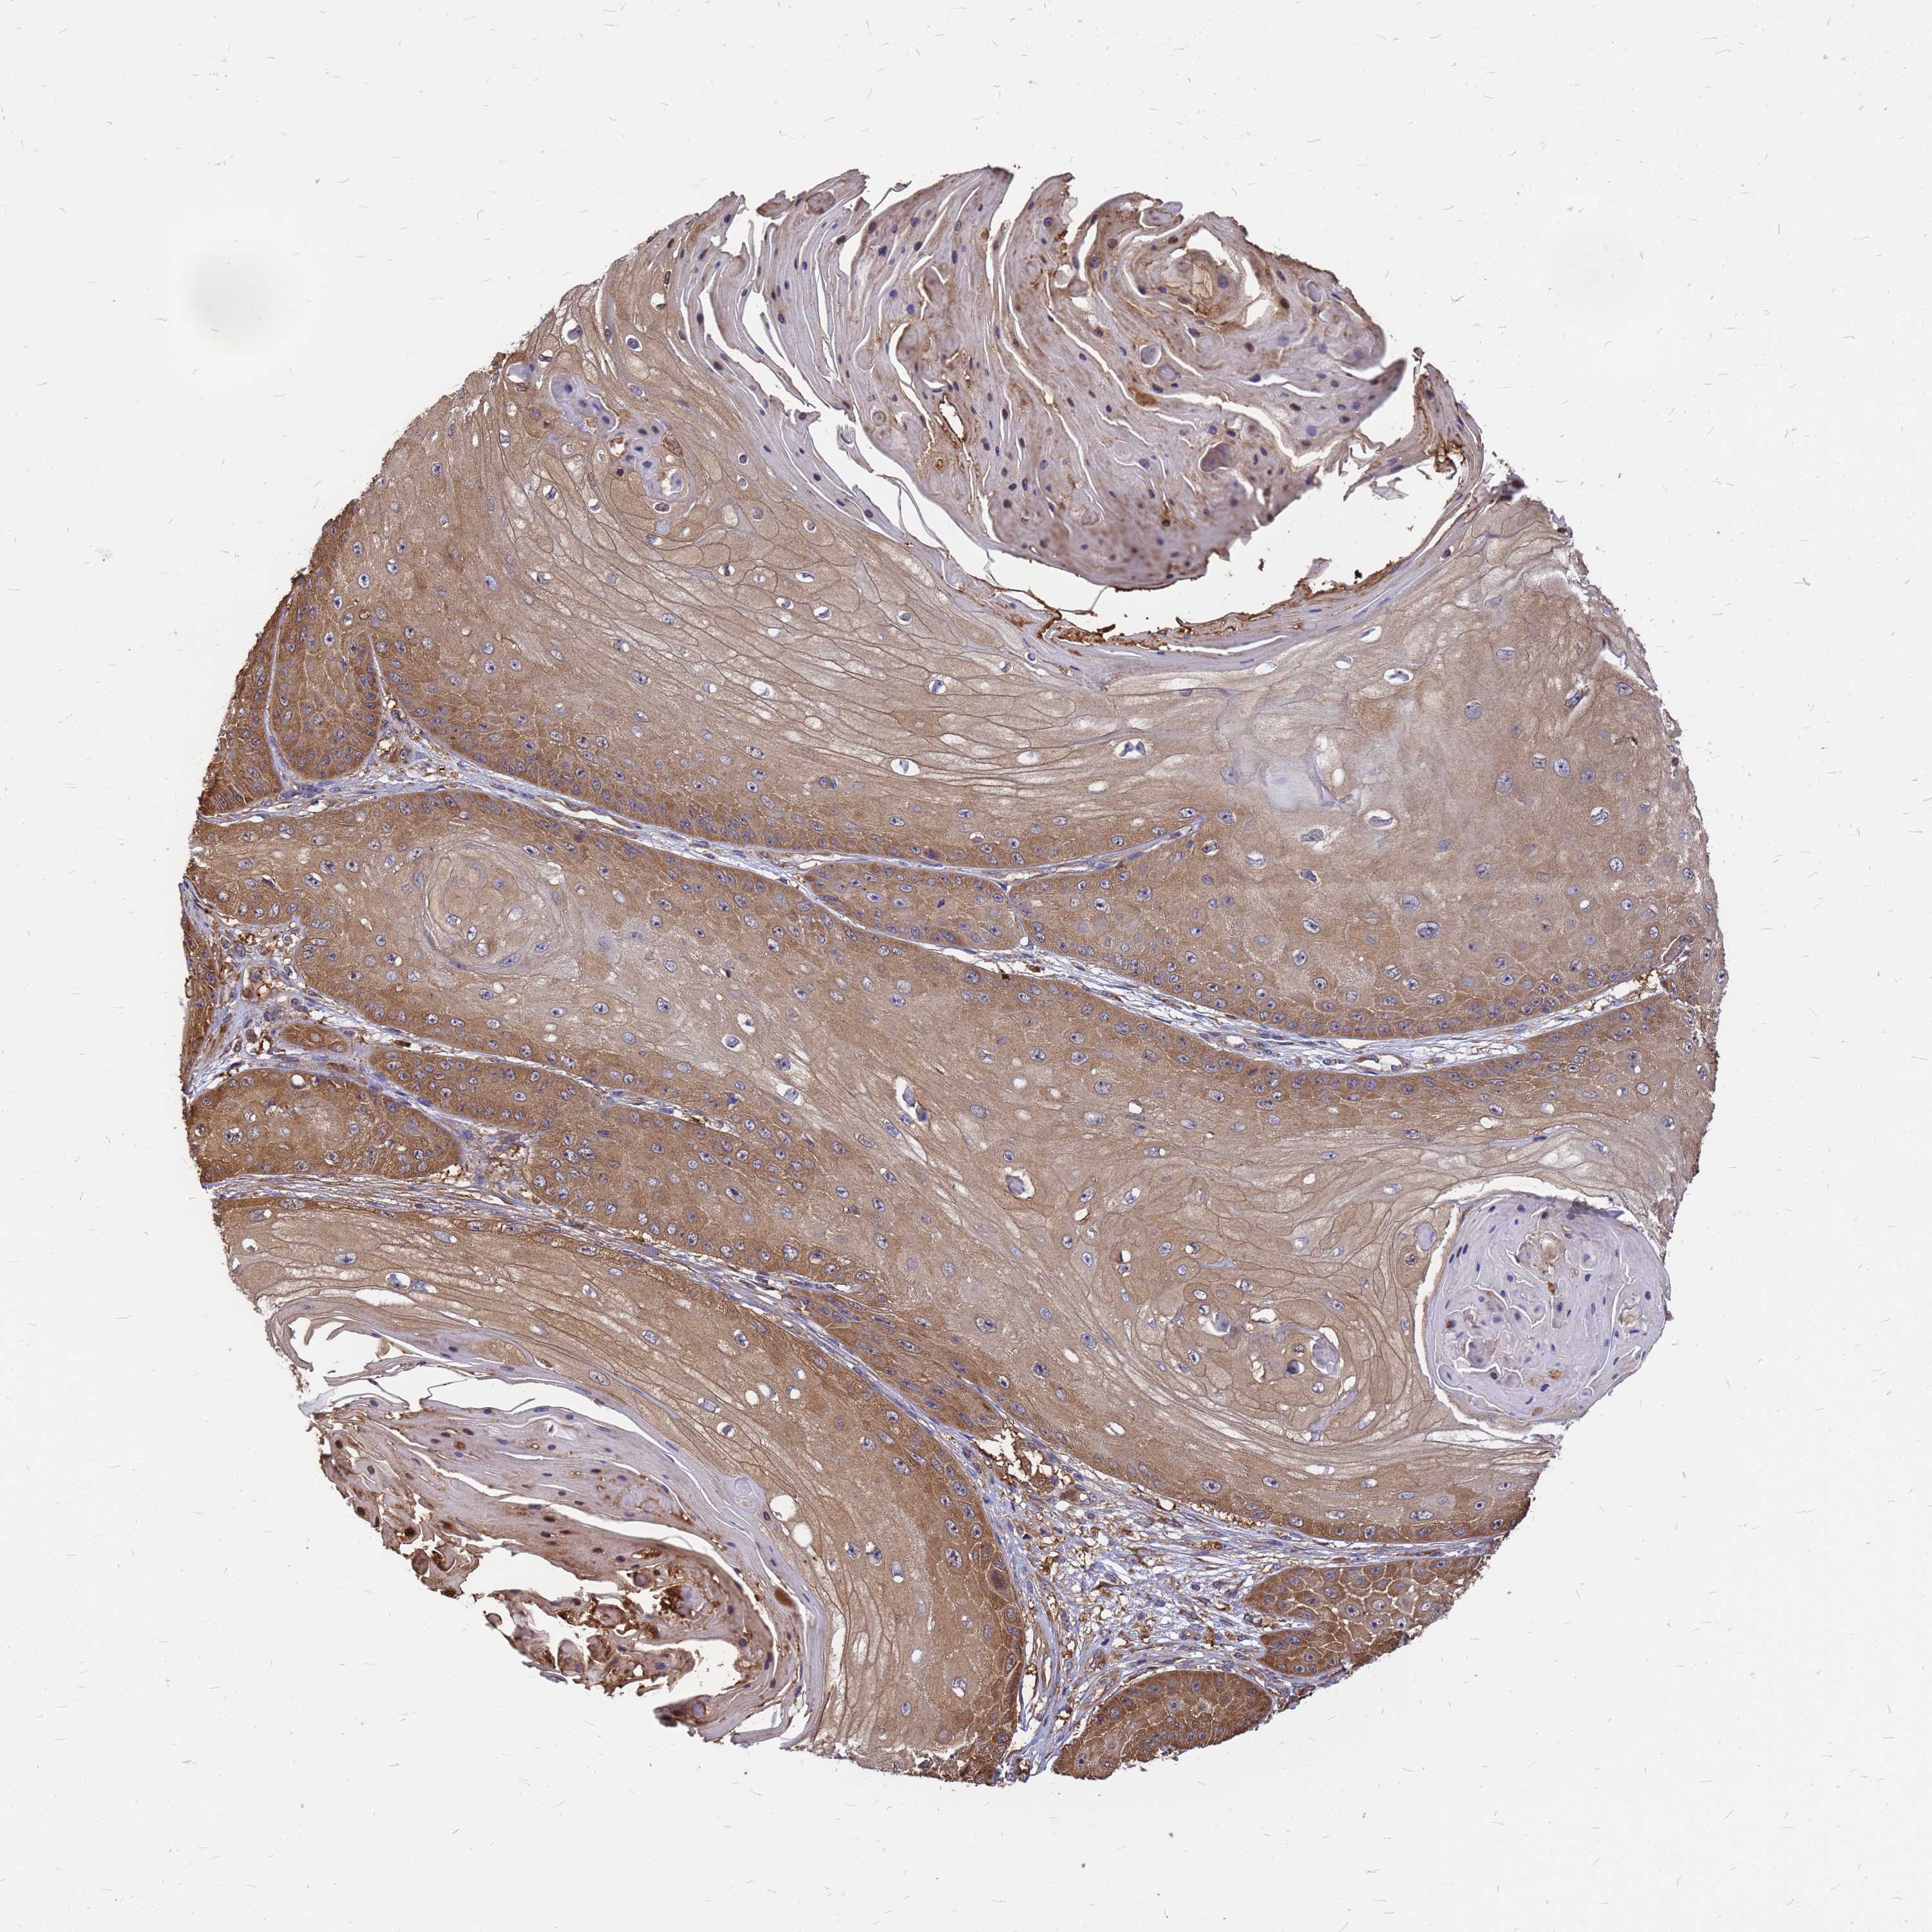

SKIN CANCER - Protein expressioni

A mouse-over function shows sample information and annotation data. Click on an image to view it in a full screen mode. Samples can be filtered based on level of antibody staining by selecting one or several of the following categories: high, medium, low and not detected. The assay and annotation is described here.

Antibody staining in the annotated cell types in the current human tissue is reported as not detected, low, medium, or high, based on conventional immunohistochemistry profiling in selected tissues. This score is based on the combination of the staining intensity and fraction of stained cells.

Each image is clickable and will lead to virtual microscopy that enables deeper exploration of all samples and also displays staining intensity scores, fraction scores and subcellular localization as well as patient and tissue information for each sample.

Antibody HPA044348

Basal cell carcinoma